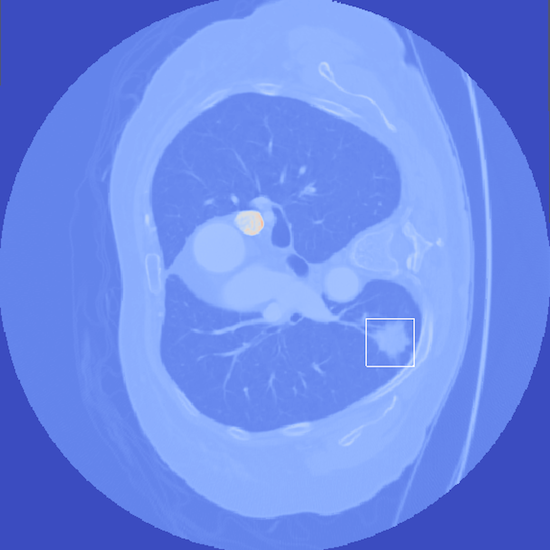

- Abstract: An exploration of whether conventional detection methods of lung cancers in low dose spiral CT scan could be improved using curvature features. In general, a large source of inaccuracy in detection rates can be attributed to irrelevant anatomical structures such as blood vessels. Often these irrelevant anatomical structures have different shape characteristics from lung nodules. For example lung nodules tend to appear bloblike as oppose to blood vessels, which appear cylindrical, or organ walls, which appear planelike. These curvature features were determined using eigenanalysis of the local second order image Hessian of each voxel, where the principal values are indicative of the local shape and provide more information than analysis performed on first derivatives alone.

- Method Overview: In each CT scan, the internal 3D lung volume was isolated using standard thresholding of pressurevalues ranges associated with lung parenchyma. The remaining voxels were conjoined using a connected components method, implemented through a union-find method, with small and isolated components removed. The remaining gaps were filled in using a standard 3D image closure method. First and second order partial derivatives were computed using Deriche filters, chosen for their stability and suitability in medical image scans. Then, for each of the voxels in the internal volume of the lung the local second order Image Hessian was generated and analyzed for preferred directions using eigenanalysis. This information was then used to weight the contribution of each voxel to standard lung nodule detection methods, to determine if giving stronger weight to voxels with local blob-like shape improved detections results.

Bottom Row: Examples of lung nodule detections.